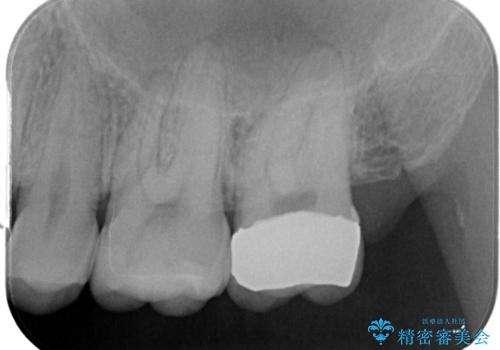

- 歯茎がよく腫れ、痛みが出ることを主訴に来院された患者様です。

レントゲン等から、金属の被せ物が歯にあって作られていないことがわかり、汚れの貯留もみられました。

金属を除去し、虫歯の治療後に型取りを行い、清掃性、審美性に優れたセラミックインレー、セラミッククラウンを装着いたしました。